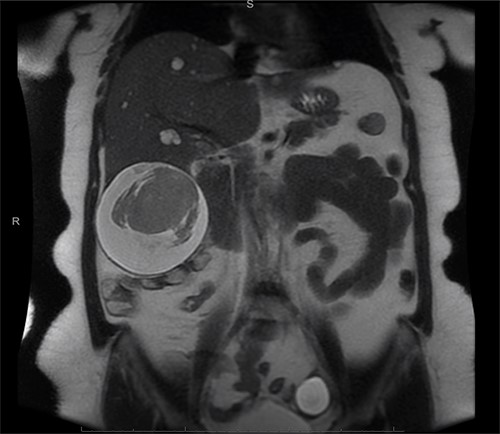

A computed tomography (CT) scan with intravenous (IV) contrast of the abdomen (Fig. 1) was performed and demonstrated a large 12 × 11 × 10 cm round exophytic complex hepatic cyst containing central soft tissue density mass and septations with multiple small hepatic cysts throughout liver. A hemorrhagic component within the cyst was also seen. In order to further delineate the cyst’s relationship to the biliary tree and surrounding structures, magnetic resonance imaging (Fig. 2) was also performed and a large exophytic peripherally cystic lesion with central solid non-enhancing component in inferior right lobe of the liver was seen. There was no evidence to suggest free rupture, communication to the biliary tree or hemobilia. The patient was admitted for close monitoring and on the third day her abdominal examination progressed to include tenderness in all quadrants of the abdomen with peritoneal signs. The patient received two packed red blood cell transfusions due to a drop in hemoglobin (12.1–8.8 g/dl) associated with tachycardia up to 131 bpm. Surgical management was discussed with the patient and she agreed to proceed.

Exophytic peripheral cystic lesion with central solid non-enhancing component in inferior right lobe of the liver.